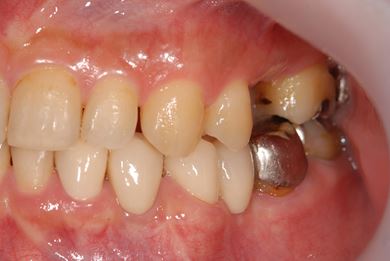

骨再生インプラント治療

| 性別/年齢 | 男性 / 34歳 | ||||||||||||||||||||||||||||||||

| 治療方針 | ソケットリフトにて上顎洞を拳上し、インプラント治療を可能にする。 | ||||||||||||||||||||||||||||||||

| 治療内容 | インプラント1本(ソケットリフト)、メタルボンドセラミッククラウン1本 | ||||||||||||||||||||||||||||||||

| 総治療費 | 547,838円 | ||||||||||||||||||||||||||||||||

| 治療期間 | 4ヶ月 |